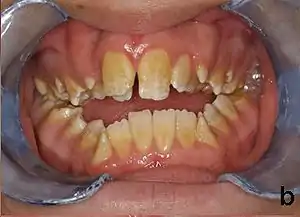

| Amelogenesis imperfecta, hypoplastic type. Note the association of pitted enamel and open bite. | |

People afflicted with amelogenesis imperfecta may have teeth with abnormal color: yellow, brown or grey; this disorder can afflict any number of teeth of both dentitions. Enamel hypoplasia manifests in a variety of ways depending on the type of AI an individual has (see below), with pitting and plane-form defects common.[4] The teeth have a higher risk for dental cavities and are hypersensitive to temperature changes as well as rapid attrition, excessive calculus deposition, and gingival hyperplasia.[5] The earliest known case of AI is in an extinct hominid species called Paranthropus robustus, with over a third of individuals displaying this condition.[6]